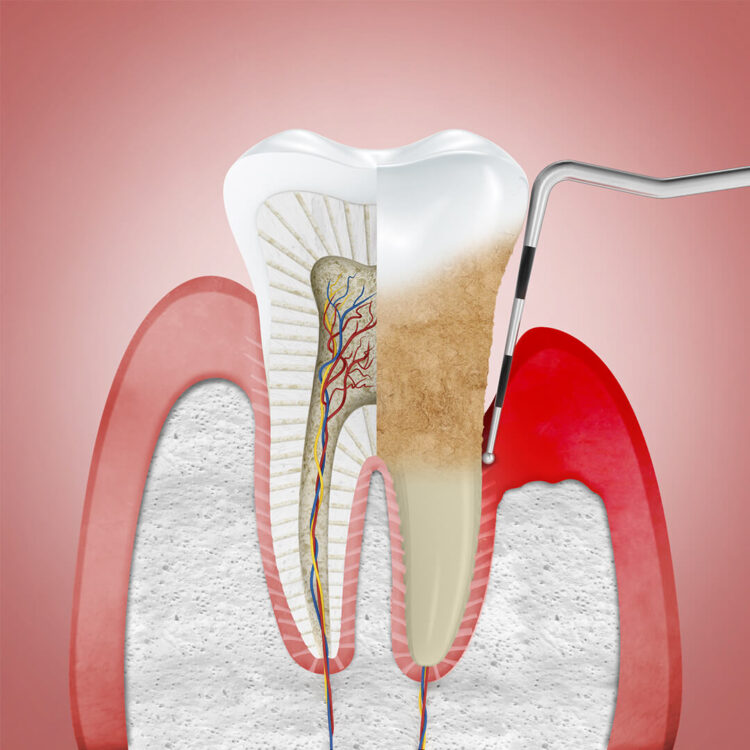

口腔衛生不佳或不正確的牙齒清潔方式是導致牙周病的主因。食物殘渣及細菌會在牙齒周圍堆積,與唾液混合形成牙菌斑。牙菌斑是一層透明的黏稠薄膜,牙菌斑細菌會產生有毒的酸性物質,引發身體的免疫反應,使牙齦紅腫發炎流血。如果沒有適當的清潔,牙菌斑會漸漸鈣化形成牙結石,牙結石的表面更容易附著大量的細菌,導致牙齦炎,最終破壞到齒槽骨,發展成牙周病。

此階段細菌已侵入齒槽骨,造成齒槽骨流失,並破壞牙周韌帶,使牙齦與牙齒之間形成一條狹窄的縫隙,稱為牙周囊袋。一旦牙周囊袋產生,牙菌斑就更容易在此堆積,牙刷將很難清潔到此處的死角,牙齦紅腫發炎的情況持續出現,並向更深處的牙周組織蔓延。

隨著細菌進一步破壞造成齒槽骨流失,牙周囊袋也越來越深,臨床上牙齦會持續發炎,甚至產生膿包。牙齒也因牙齦萎縮而使牙根暴露,容易對冷熱敏感,牙齒外觀看起來變長了,牙根之間出現縫隙,患者可能會感到咀嚼時無力,且牙齒咬合方式改變。

齒槽骨因嚴重破壞而大量流失,幾乎無法支撐牙齒,造成牙齒大幅度搖動、鬆脫,甚至明顯移位。牙齦不定期的化膿腫大,口臭味道加劇,最終牙齒自然脫落或拔除。